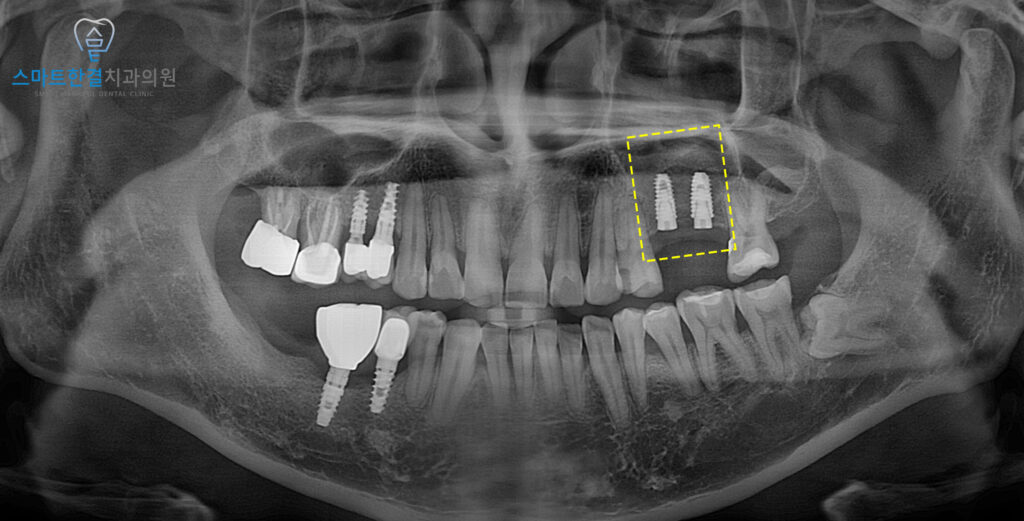

<안정적인 임플란트 식립>

상악동 거상술과 함께 진행하면

치유 기간을 더 충분히 기다려야 하며,

골이 안정적으로 형성되는 동안

무리한 저작을 피하고 정기적인 내원 관리를 통해

회복 상태를 확인하는 과정이 중요한데요.

또한 수술 부위의 압력이 과도하게 증가하지 않도록

코를 세게 푸는 행동이나

강한 외부 자극은 일정 기간 주의가 필요해요.

이와 같은 주의사항을 잘 지켜주신다면

골이식된 부위가 안정적으로 자리 잡는 데 도움이 되며,

이후 식립된 임플란트 또한

장기적으로 건강하게 유지하는 데

긍정적인 영향을 기대할 수 있는 점을 설명드리고

마무리 하였습니다.